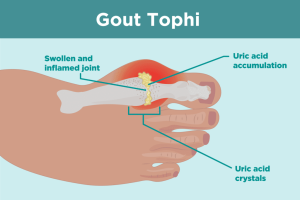

- مرحله مزمن: تشکیل رسوات زیرپوستی (توفوس) و آسیب مفصل